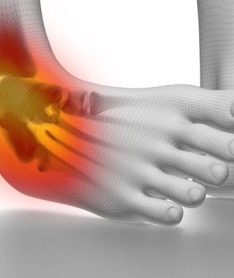

During an ankle sprain, the ligaments of the outer part of the ankle (Ex: Anterior Talo-fibular ligament or Calcaneo-fibular ligament) become stretched, partially torn, or completely torn. If the sprain is severe enough, you may damage the ligaments on the inside part of the ankle (Deltoid ligaments).

• Grade I: Lateral (outer ankle) ligaments are strained (overstretched). You ankle will tender and you may have a slight swelling. You will be able to walk with mild tenderness.

• Grade II: Partial tearing of one or several of these ligaments. You will develop moderate pain, swelling, and bruising around the ankle. You may or may not be able to bear full weight with this type of injury.

• Grade III: Complete rupture (tear) one or more of the ankle ligaments. You will have severe pain, swelling, and bruising around the ankle. You may hear a pop, indicating a torn ligament. You will not be able to bear any weight on the foot after this type of injury.